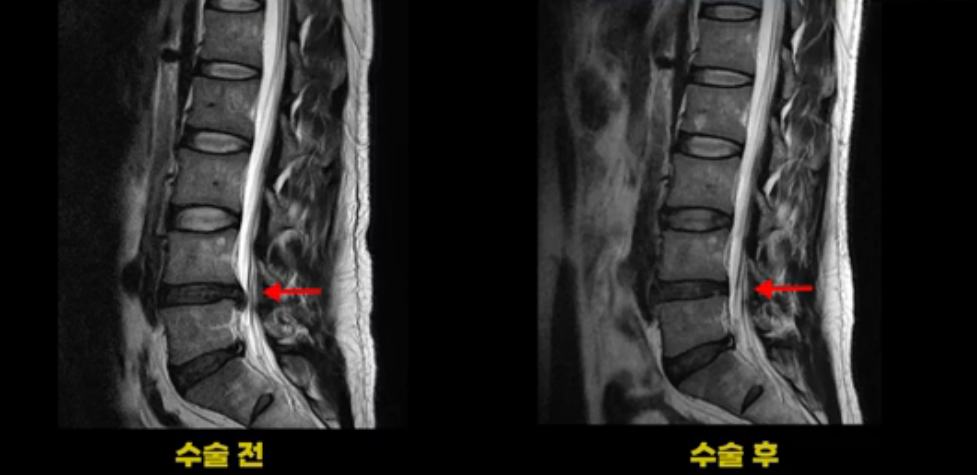

이 환자분은 디스크 파열 수술 후 3개월 정도 괜찮았다가 그 이후 점점 다리 저림과 통증이 다시 시작되어 수술 후 1년 정도부터는 거의 수술 전에 아팠던 정도까지 증상이 악화됩니다. 그런데 이분 수술 후 MRI를 보면 수술이 잘 돼서 깨끗합니다.

보시다시피 수술 전의 MRI와 비교해 보면 밀려 나온 디스크 수핵이 거의 대부분 깨끗이 제거되었습니다.

저희가 여러분께 계속해서 디스크든 협착이든 수술이 잘 되었는데도 계속 아프다면 그땐 근육 문제일 가능성이 매우 높다고 계속해서 말씀드리고 있지 않습니까? 이런 환자분이야말로 근육 문제를 의심해 봐야 합니다.